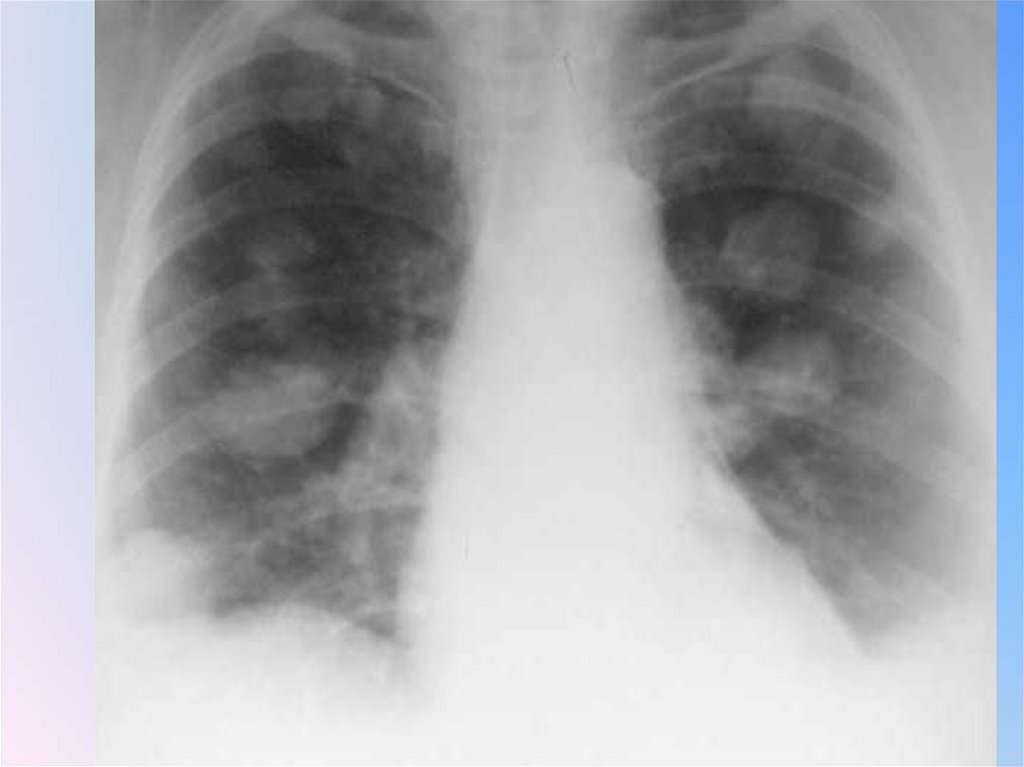

Патоморфологический субстрат шаровидного

образования: 1) туберкулезный инфильтрат;

2) туберкулома (инкапсулированный казеоз);

3) заполненная блокированная туберкулезная

каверна; 4) силикотические узлы; 5) «круглая»

неспецифическая пневмония; 6) недренированный абсцесс; 7) злокачественные опухоли;

лимфомы; 9) доброкачественные опухоли

(наиболее часто гамартомы, содержащие

хрящевую ткань); 10) сосудистые

образования; 11) кисты, заполненные

жидкостью; 12) инфаркт; 13) гематома; 14)

осумкованный экссудат в междолевой плевре

(последний не является истинно легочным, внутрипаренхиматозным образованием, однако, замкнутый листками плевры,

оказывается расположенным внутри легкого)